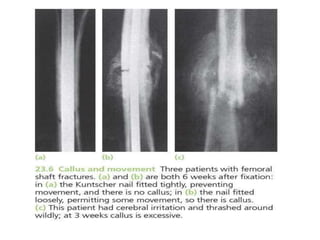

BONE HEALING

• PRIMARY FRACTURE HEALING

refers to fractures treated operatively

without callus formation

• SECONDARY FRACTURE HEALING

refers to (a) fractures treated non-

operatively, with the formation of callus and

no disturbance of hematoma; (b) fractures

operated without disturbance of hematoma

• STAGE 3: CALLUS FORMATION

- lasts for 4-12 weeks

- granulation tissue differentiates

and creates osteoblasts, laying

down intercellular matrix

impregnated with calcium salts

- formation of callus/woven bone

- provides good strength to the fracture,

decreasing the movements at the

fracture site and causes union in

about 4 weeks

HEALING BY DIRECT

UNION

• Formation of callus requires stimulus

from movement

• In cases of impacted fracture in

cancellous bone or a fracture

immobilised by the use of metal plate,

callus will not be formed and hence the

fracture will heal by direct union